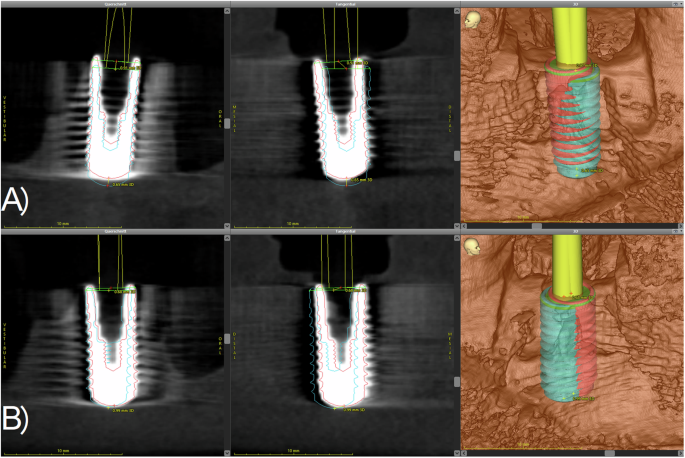

After the hands-on course, a CBCT of each model was performed using the same parameters as described above. The DICOM data sets were imported into the planning software. Using the “treatment evaluation” tool of the software, the virtual planned implant position and the CBCT scan of the manually inserted implants were superimposed as described previously [15, 16]. Next, the outline of the implants was congruently placed over the radiographical image of the achieved implant position (Fig. 2). After matching the data, the software calculated the horizontal, sagittal, vertical and three-dimensional mismatch at the implant base and tip and the three-dimensional deviation between the planned and implant positions achieved by the participants. In order to minimize matching errors, each measurement was performed three times. All values and the data obtained from the questionnaires were recorded in an MS Excel® chart (Microsoft Inc., Redmond, Washington, USA). The exemplary flow of the study is depicted in Fig. 3.